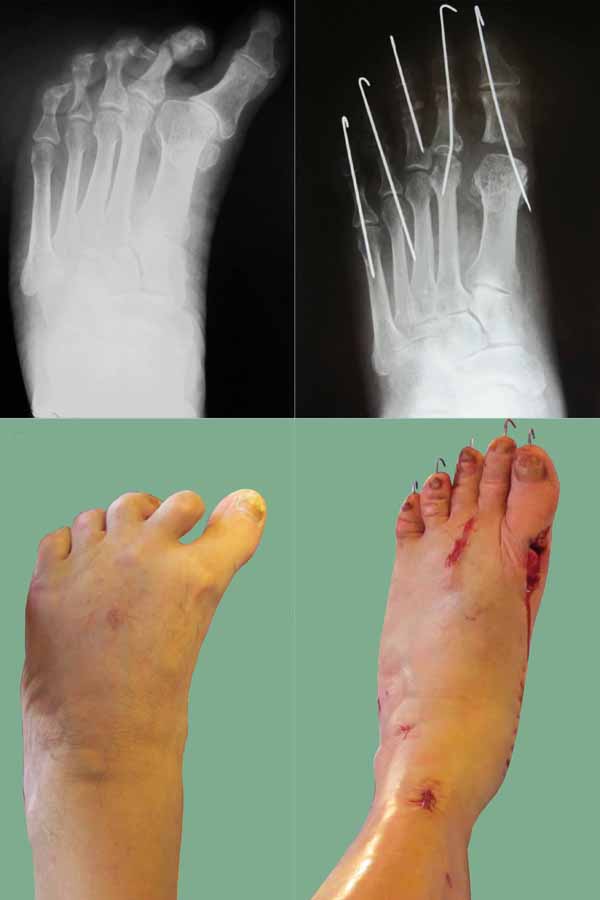

Могу сообщить из личного опыта. Больной 65 лет, страдает артрогрипозом. Стопы не оперированы. Рентген аналогичный. Деформация стопы многокомпонентная многоплоскостная: эквино-поло-варусная, приведение переднего отдела, варусная когтеобразная деформация 1 - 5 пальцев.

Выполнено:

1) удлинение ахиллова сухожилия по Байеру;

2) Z-обр. удлинение сухожилия задней большеберцовой мышцы, транспозиция сухожилия передней большеберцовой мышцы на наружный край стопы;

3) пересечён подошвенный апоневроз;

4)Z-обр. удлинено сухожилие длинного сгибателя 1 пальца, тенотомия сухожилия сгибателей 2 - 5 пальцев;

5)транспозиция сухожилия длинного разгибателя 3 п. на длинный разгибатель 2 п. с удлинением, транспозиция короткого разгибателя на длинный 3 п. с удлинением;

6) капсулотомия 2 - 3 ПФС, круговой релиз 1 ПФС;

резекция основания проксимальной фаланги 1 п.

Фиксация 1 - 5 пальцев осевыми спицами. Лонгета. Ближайший результат на фото (операция 8 дней назад).

Олег! Что за рана в области 1 ПФС через 8 суток после операции? На фото четко не вижу, но, по-моему, в ране- головка плюсневой кости?!

Фото на операционном столе, рана в области 1 ПФС ещё не зашита. Постараюсь выложить новые фото по мере заживления.